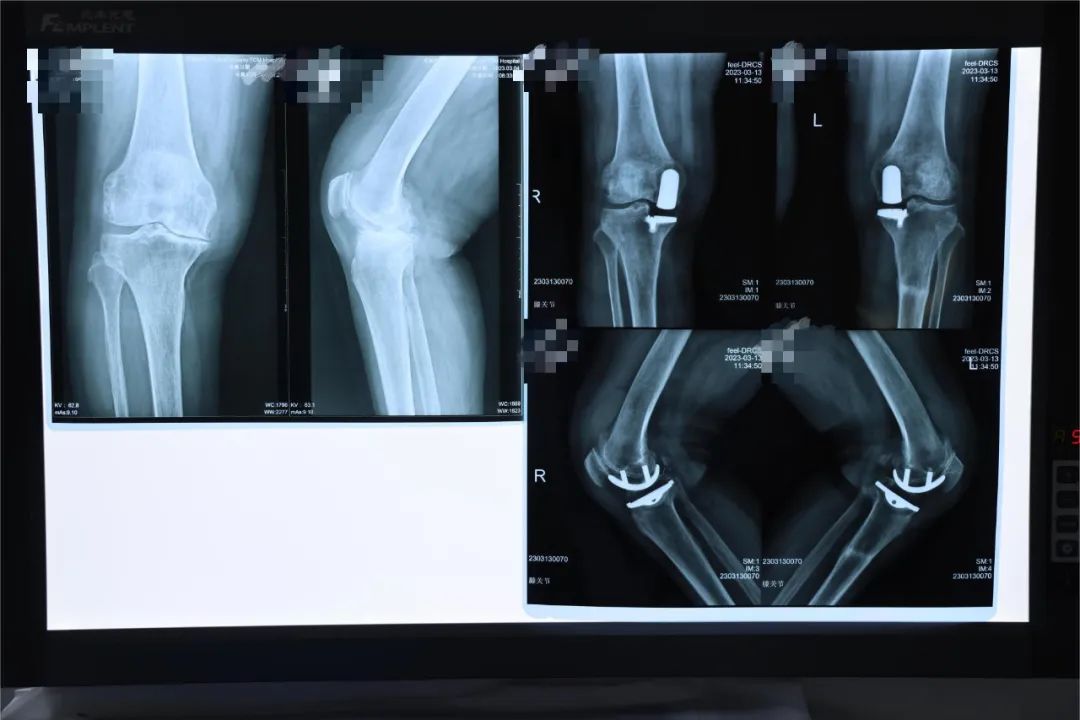

双侧人工膝关节置换

(浅谈一例双膝关节严重畸形患者行双膝关节置换术效果)

双膝关节置换

其它 膝关节"重生" 写美篇 患者术前存在严重的双膝关节内翻

患者 男性 78岁,双膝关节疼痛10年,入院诊断:双膝关节退行性病变.

患者术前双膝关节屈曲畸形,伸屈受限,行走困难